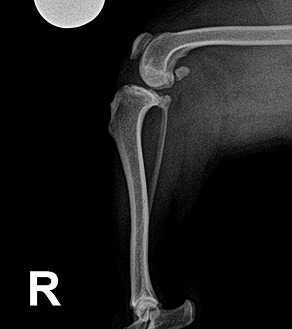

BEFORE